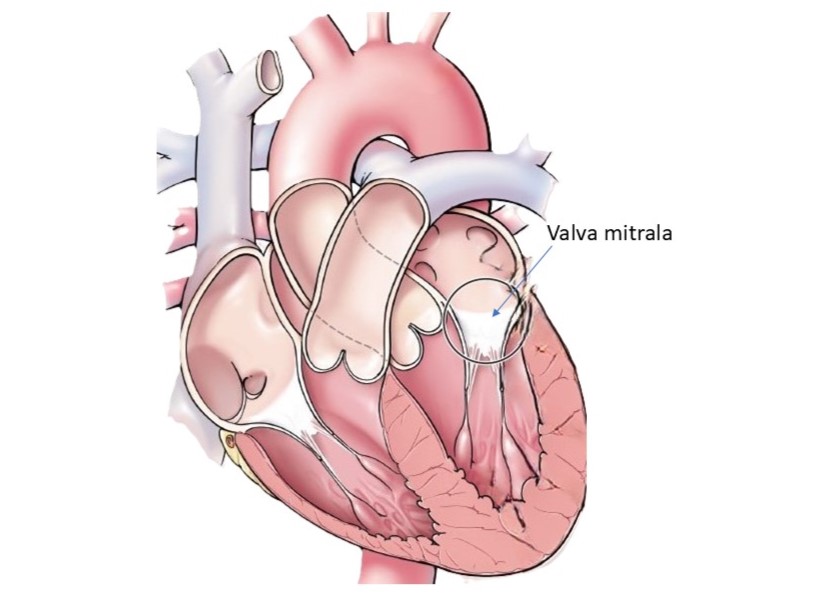

Când foitele valvei mitrale nu se închid perfect, sângele din ventriculul stâng se întoarce (refuleaza) in atriul stâng si catre plamâni. Această situație poartă nume de insuficienta sau regurgitare mitrala. Regurgitarea mitrala poate evolua încet (insuficientă mitrala cronica) si la mulți dintre pacienți s-ar putea sa nu apară simptome importante. Alteori boală poate aparea brusc și se numește insuficientă mitrală acuta. Simptomatologia în acest caz se instalează rapid și zgomotos. Dificultatea in respiratie (dispneea) progresiva la efort si uneori si in repaus, in pozitia culcat, chiar si noaptea, este unul dintre primele semne ale bolii desi nu este specific. Alte semne sunt:

Exact opusul insuficienței mitrale, stenoza valvei mitrale este prezentată prin deficitul de deschidere a valvei fie prin blocarea mișcărilor acesteia fie prin micsorarea orificiului valvei. În această situație sângele rămâne partial blocat in atriul stang si în plămâni, cu apariția dispneei, toleranței scăzute la efort, hipertensiune pulmonara, dificultatea la respirație accentuandu-se în pozitia culcat. Responsabile pentru apariția stenozei mitrale sunt reumatismul și modificări degenerative cu calcificări importante de inel si de cuspe ale valvei mitrale. De cele mai multe ori, afectarea valvei mitrale este dubla, coexistand stenoza si insuficienta, datorita modificarilor structurale importante ale acesteia, afectiunea numindu-se boala mitrala.